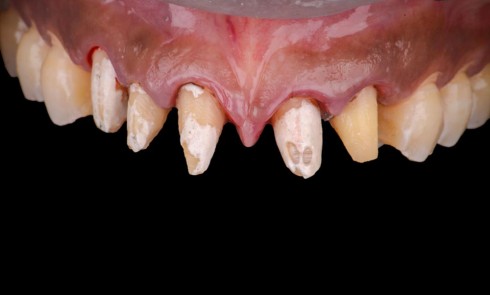

Prothèse implantaire, temporisation et restauration de la mastication et du sourire chez une patiente bruxomane

Quels sont les problèmes posés par le bruxisme ? Comment peut-on placer des implants sur un patient bruxomane ? Pourquoi utiliser un articulateur adaptable ? Comment mener la chronologie du traitement ?